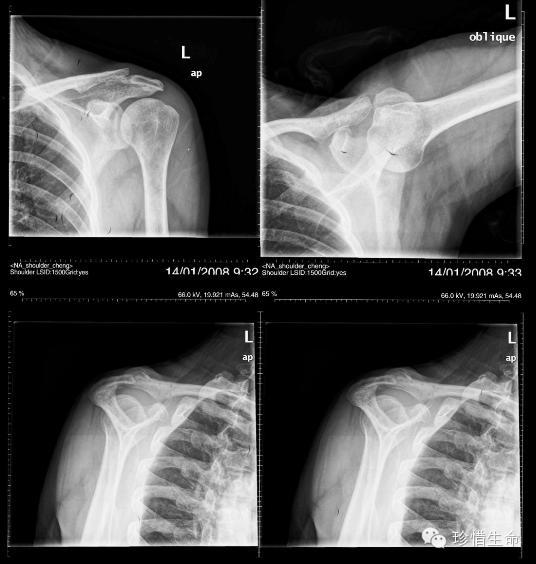

术后左肩x线侧位片

肩关节的x线照片或x线照片.另外一个视图名是冈上出口